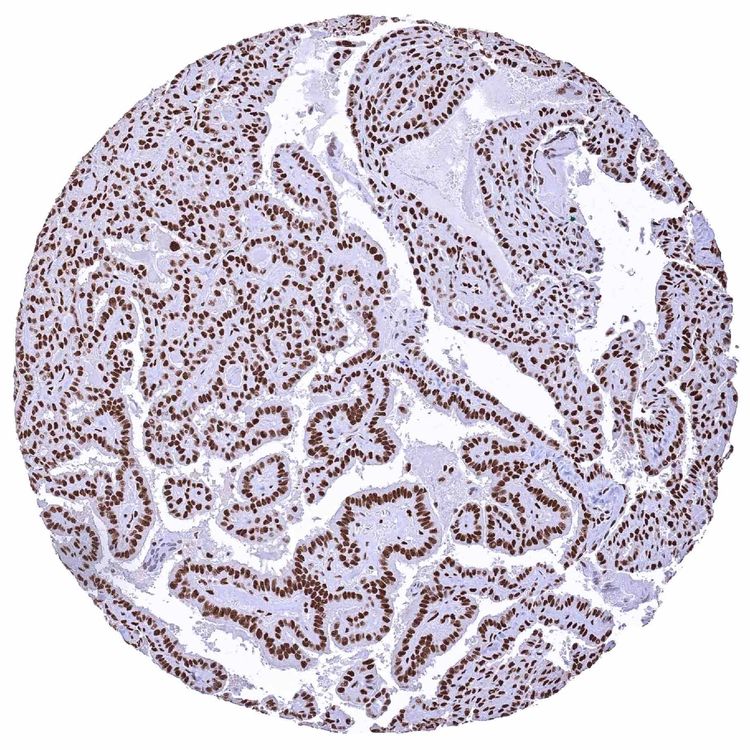

Ovary

Ovary – Serous high-grade carcinoma with a strong nuclear MRE11 staining of tumor cells